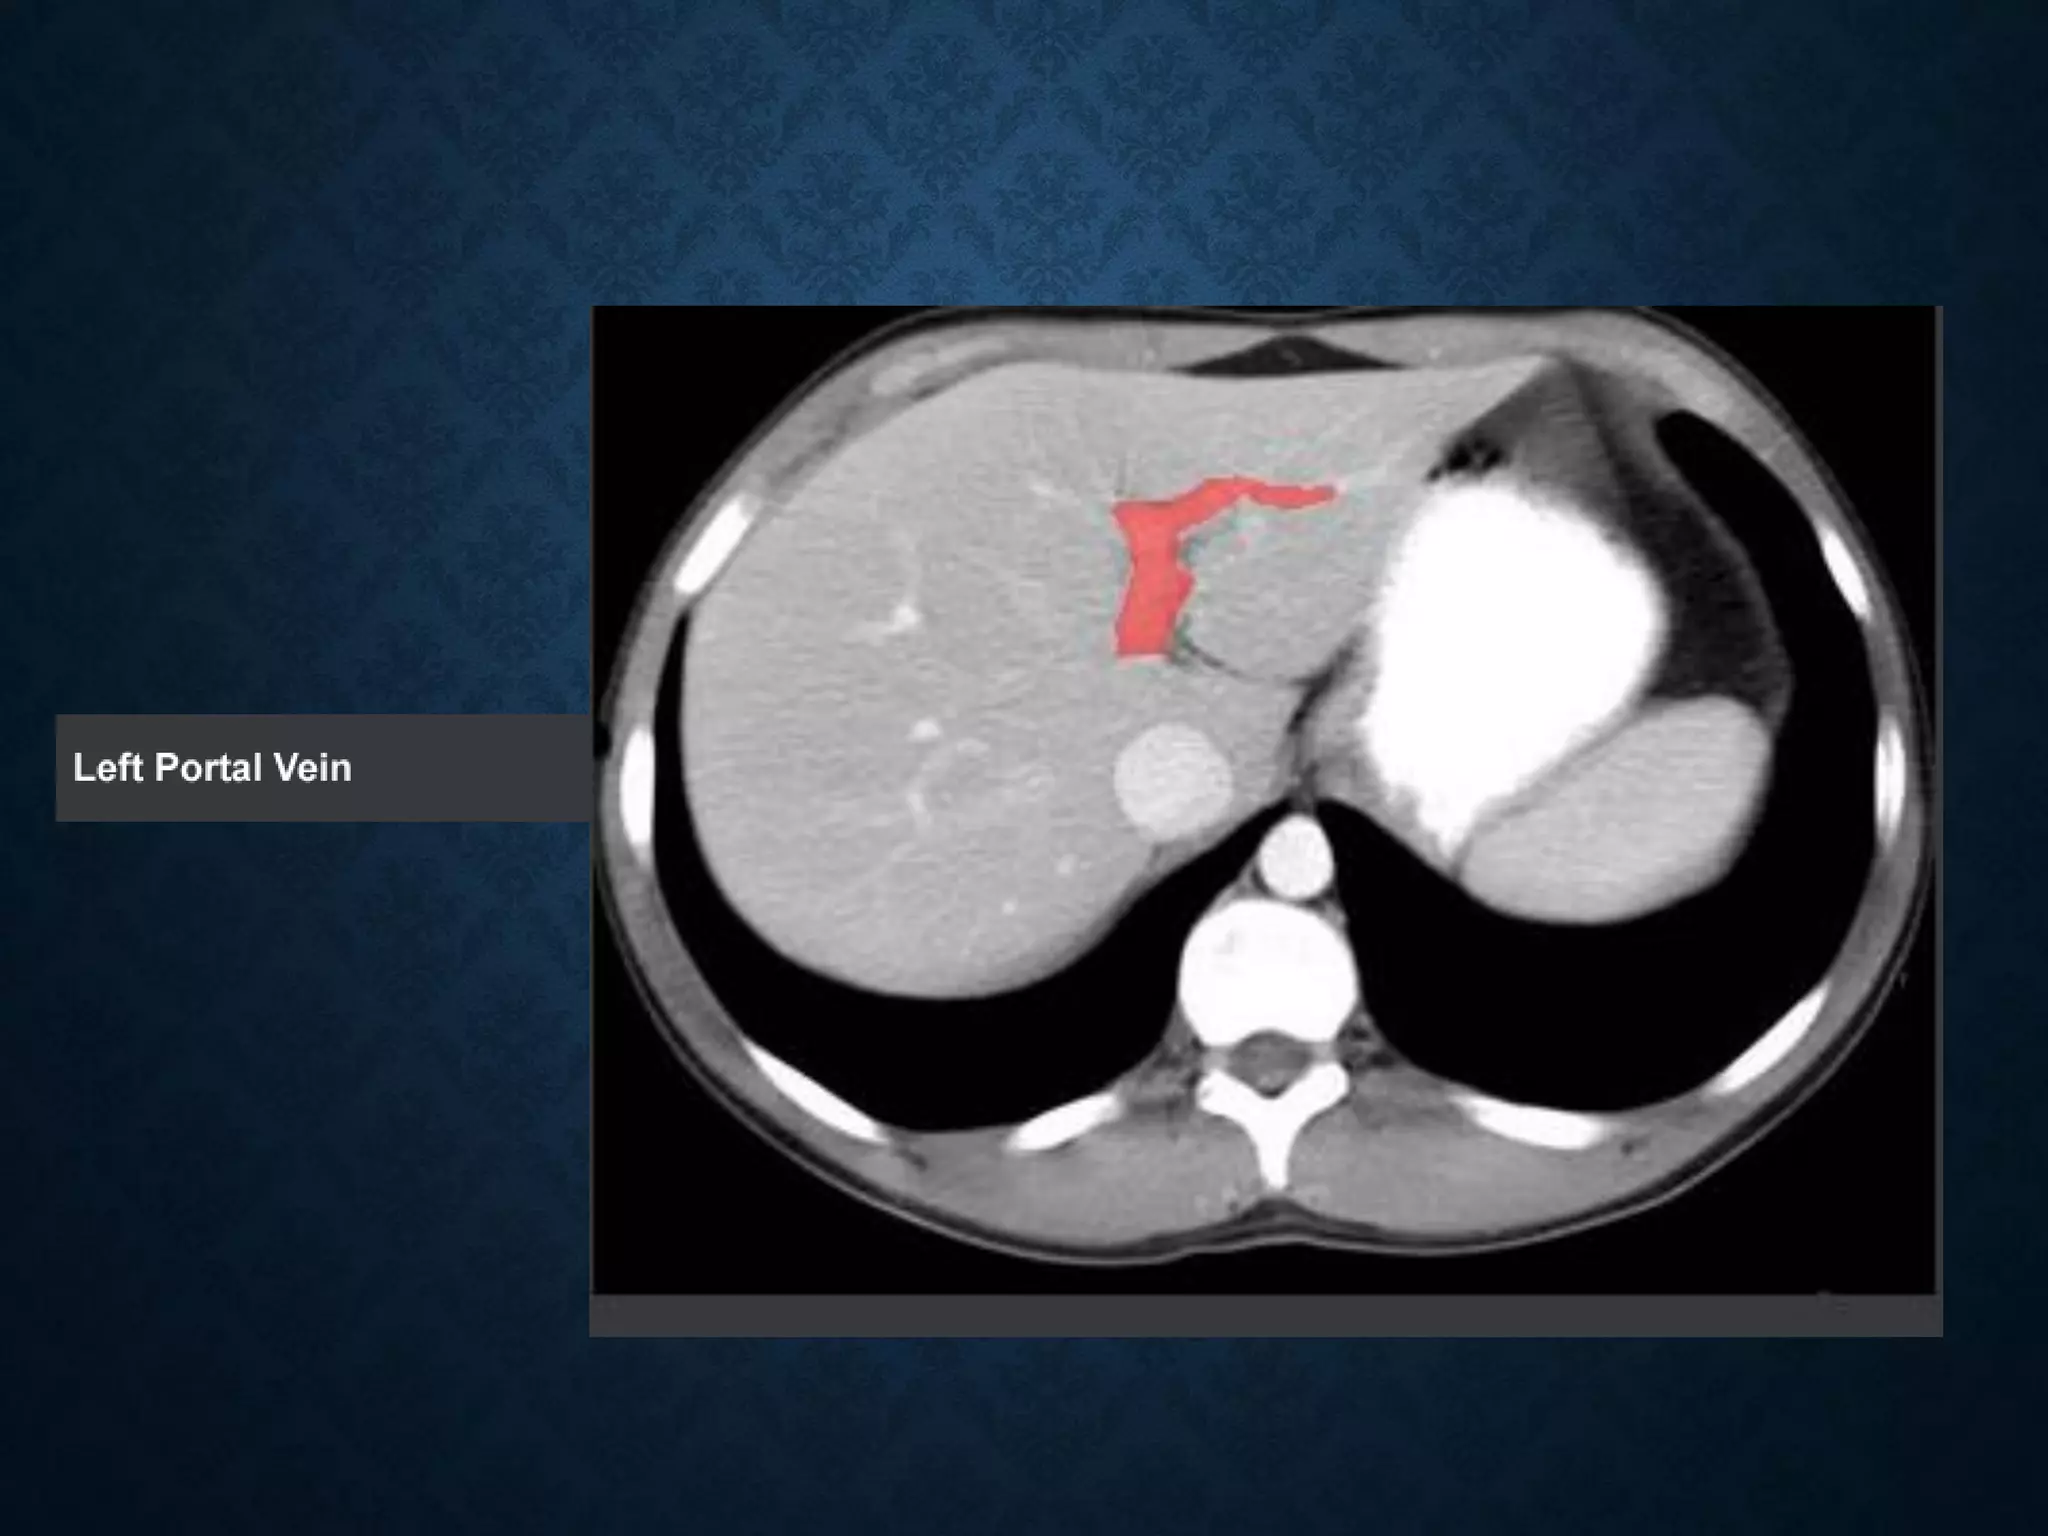

Identify the following structures in the body CT to the right. To view the location of the structure in the image click on

the label at the left and the structure will be indicated in the image. Abdominal CT scans typically begin just above

the diaphragm, so the first slice you see is of the lower chest.